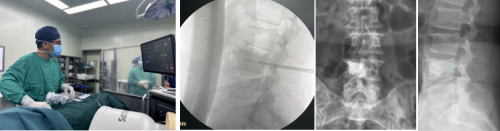

图2:手术中操作、透视确定消融针位置、术后复查X线片

腰椎转移瘤患者为60岁女性。肺腺癌骨转移,腰背部疼痛有接近一月,直不起腰,不敢翻身,疼痛剧烈,疼痛评分8分,磁共振成像显示腰4椎体转移瘤。为解决患者的疼痛症状,团队决定实施复合式冷热消融、椎体成形手术。经过麻醉手术部的大力配合,顺利地完成了“冷”与“热”消融、椎体成形手术,术后患者双下肢功能正常,腰背部疼痛得到明显改善,疼痛评分降至2分。